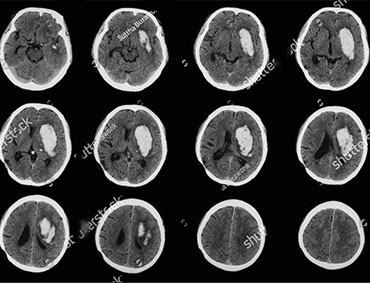

Brain tumor or intracranial neoplasm occurs when abnormal cells form within the brain. There are two main types of tumors: malignant or cancer

ous tumors and benign tumors. Cancerous tumors can be divided into primary tumors that start within the brain, and secondary tumors that have spread from somewhere else, known as brain metastasis tumors. All types of brain tumors may produce symptoms that vary depending on the part of the brain involved.

Tumors depend on their size, type, and location. The most common symptoms of brain tumors include headaches; numbness or tingling in the arms or legs; seizures, memory problems; mood and personality changes; balance and walking problems; nausea and vomiting; changes in speech, vision, or hearing.